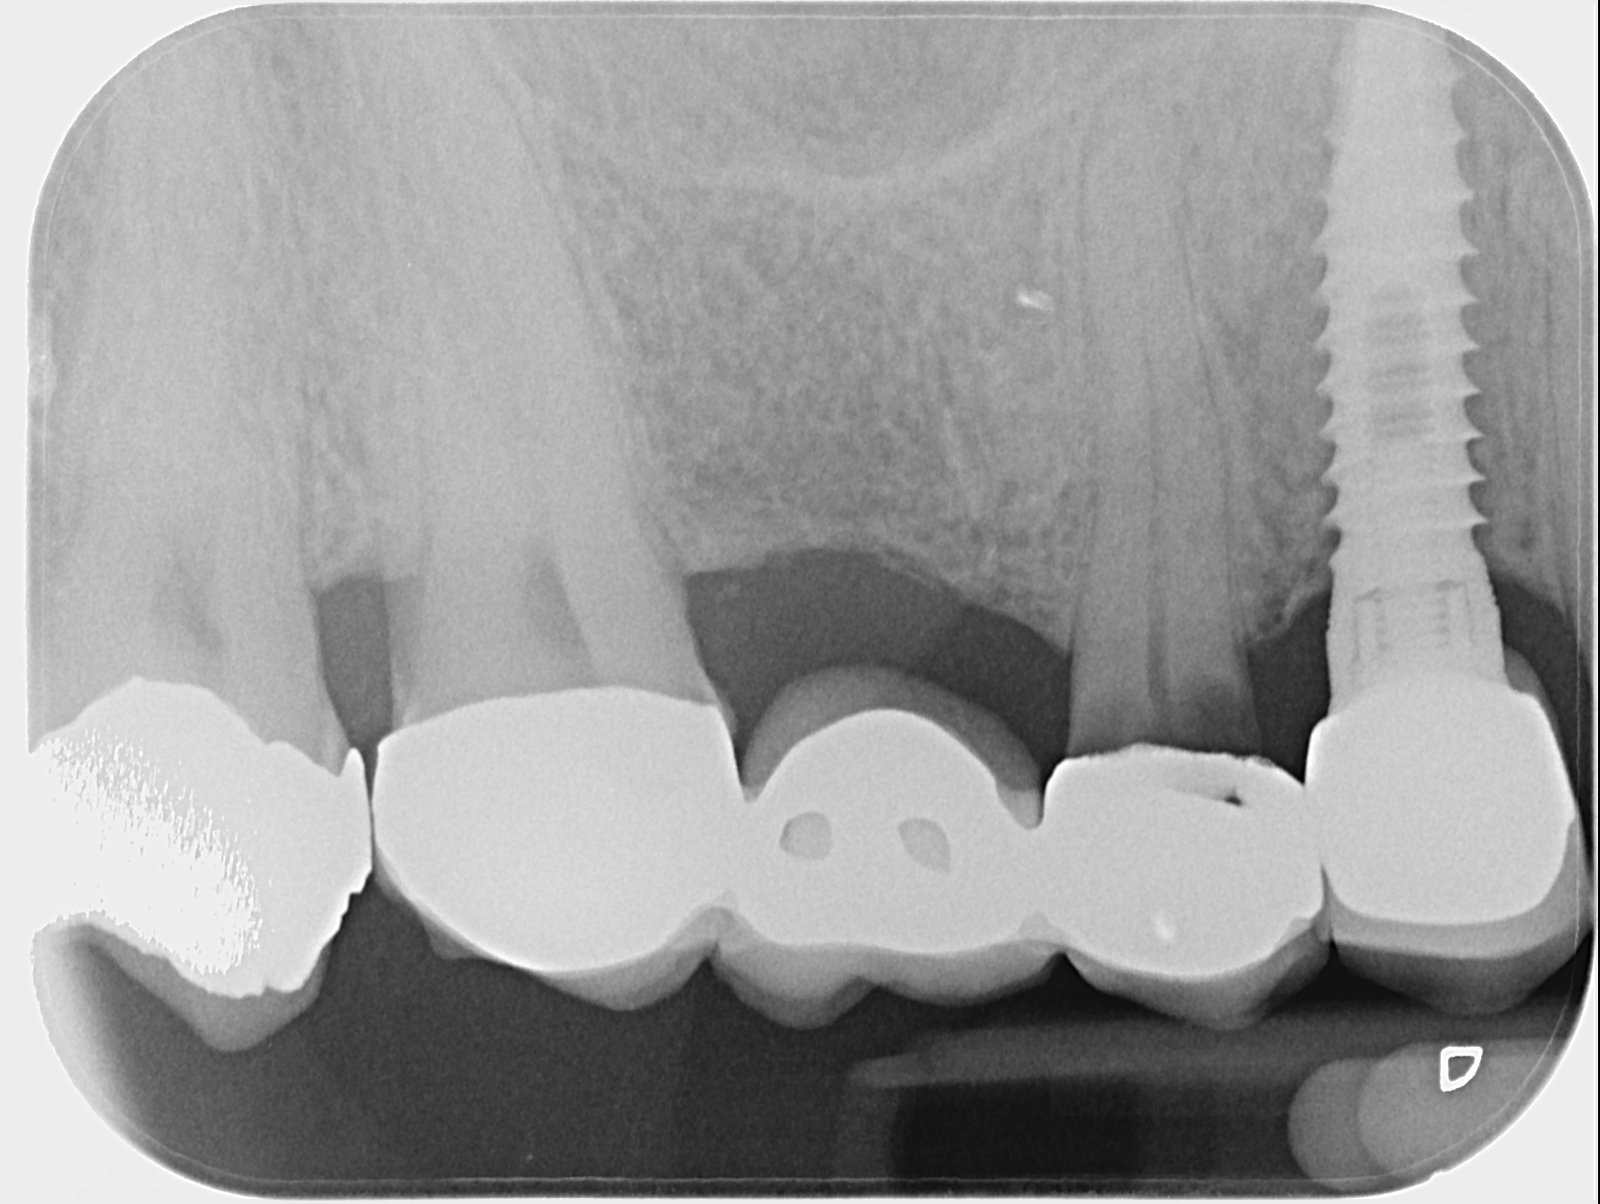

La paciente ha acudido a la clínica en numerosas ocasiones porque se le mueve la corona del implante del 46. Ninguno de los destornilladores que tengo en la clínica termina [...]